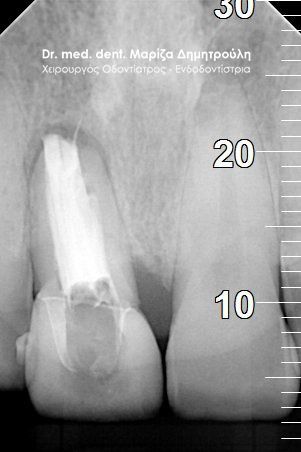

Root canal retreatment

AFTER